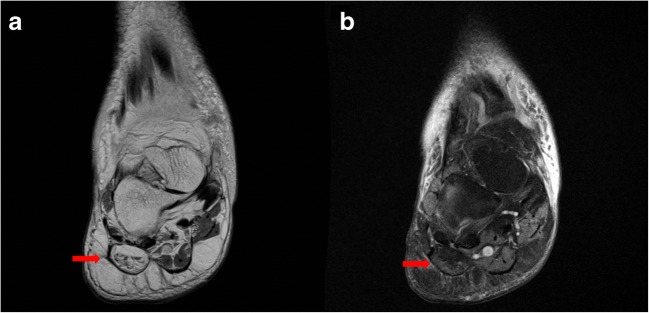

MRI is useful in identifying lateral plantar nerve entrapment through detection of muscle alterations associated with denervation [72]. In acute and subacute muscle denervation, fluid-sensitive MRI sequences, specifically proton-density and T2-weighted sequences, demonstrate hyperintense signal within the abductor digiti quinti muscle, corresponding to neurogenic muscle edema (Fig. 13a, b) [72]. Chronic denervation leads to atrophy and irreversible fat infiltration that are well depicted on T1-weighted images, demonstrating significant volumetric reduction of the abductor digiti quinti muscle with occupied fatty tissue. Through clear depiction of osseous and soft tissue structures in the heel region, MRI provides highly accurate diagnostic methods to evaluate for lateral plantar nerve entrapment [24].

Fig. 13.

Coronal proton-density (a) and proton-density fat-saturation (b) images demonstrate fatty infiltration of the abductor digiti minimi muscle belly (arrows), indicative of lateral plantar nerve entrapment (Baxter’s neuropathy).

As with management of plantar fasciitis, that of lateral plantar nerve entrapment focuses on conservative methods including rest, activity modification, NSAIDs, stretching exercises, and local steroid injections [51]. Although the literature on long-term outcomes is limited, surgical release of the fascia overlying the abductor hallucis via open or endoscopic decompression is warranted after conservative treatment fails [51].